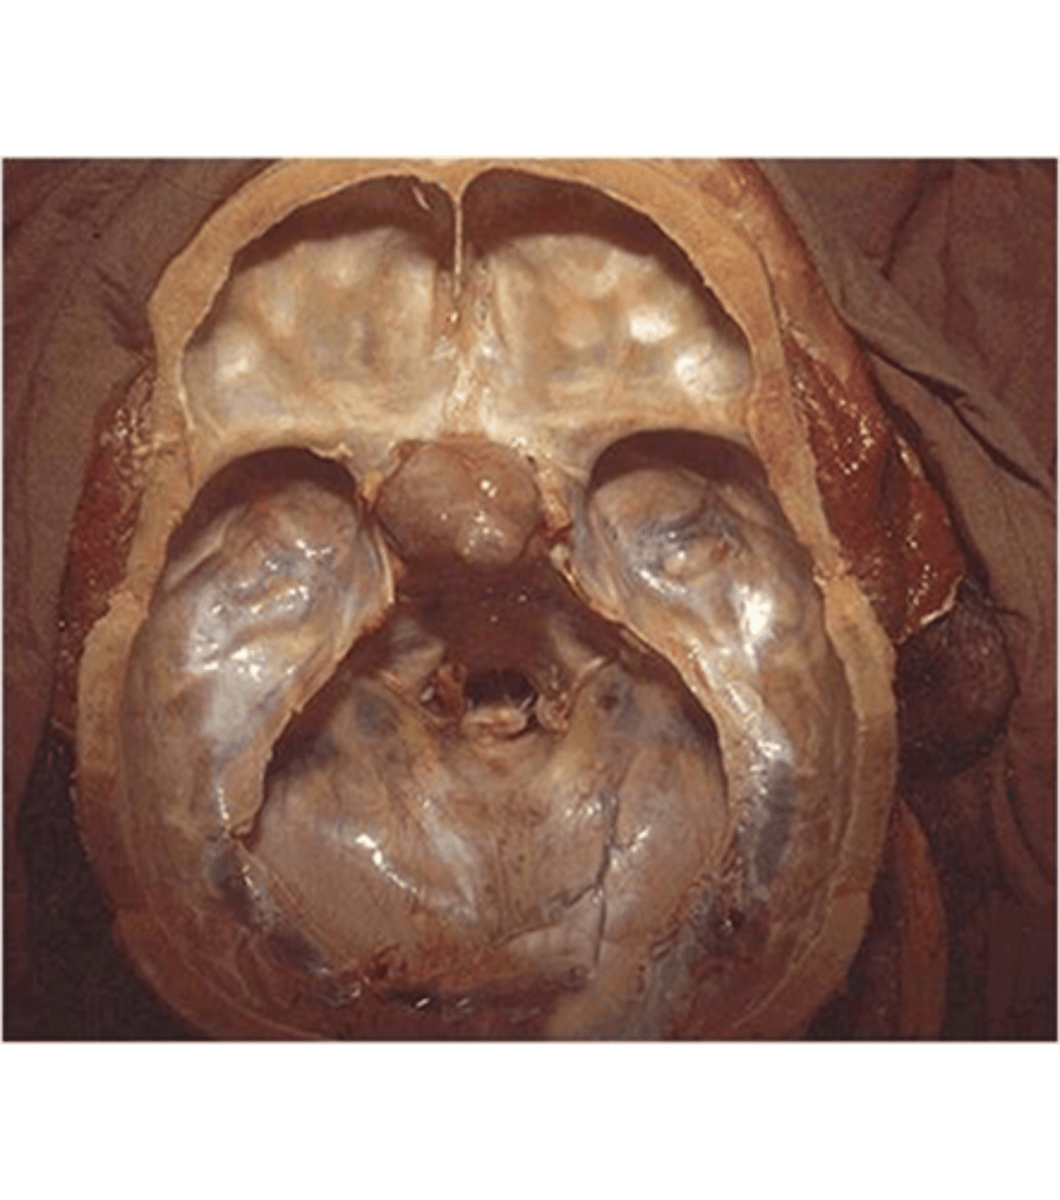

Waterhouse-Friderichsen syndrome

pathology?